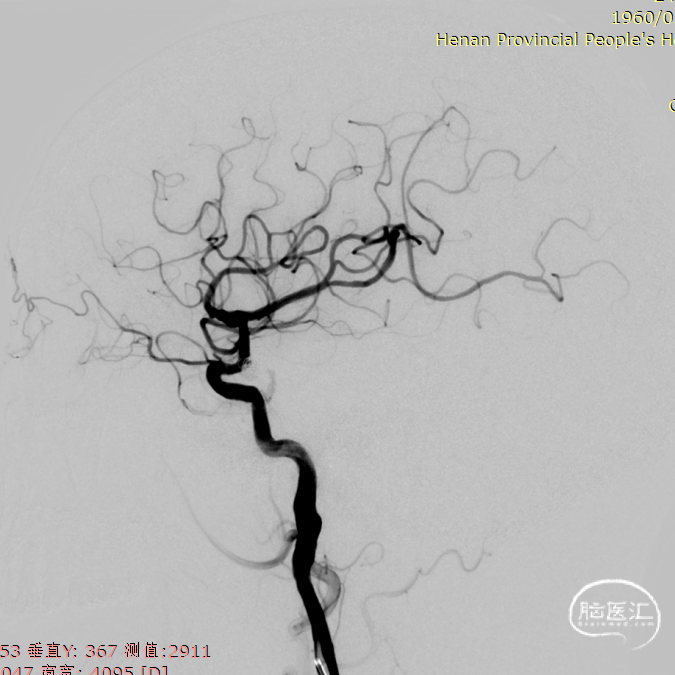

DSA造影显示右侧颈内动脉后交通动脉瘤,栓塞术后即刻及术后6月随访影像。

DSA造影显示左侧颈内动脉眼动脉动脉瘤,动脉瘤累及眼动脉开口,形态欠规则,颈内动脉颈段迂曲。

工作角度展示动脉瘤颈。